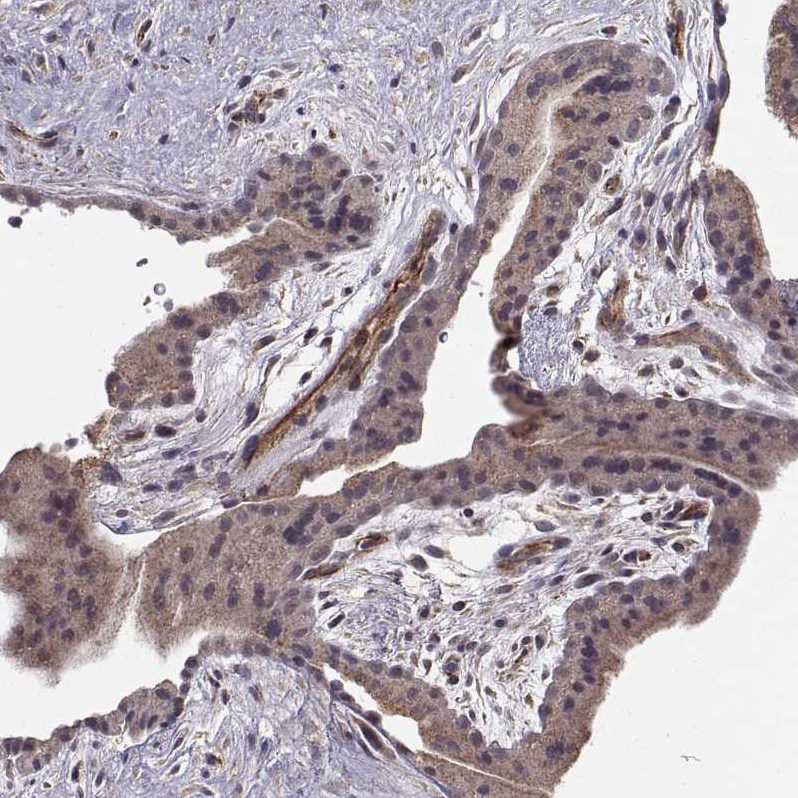

Immunohistochemical staining of human gallbladder shows moderate cytoplasmic positivity in glandular cells.